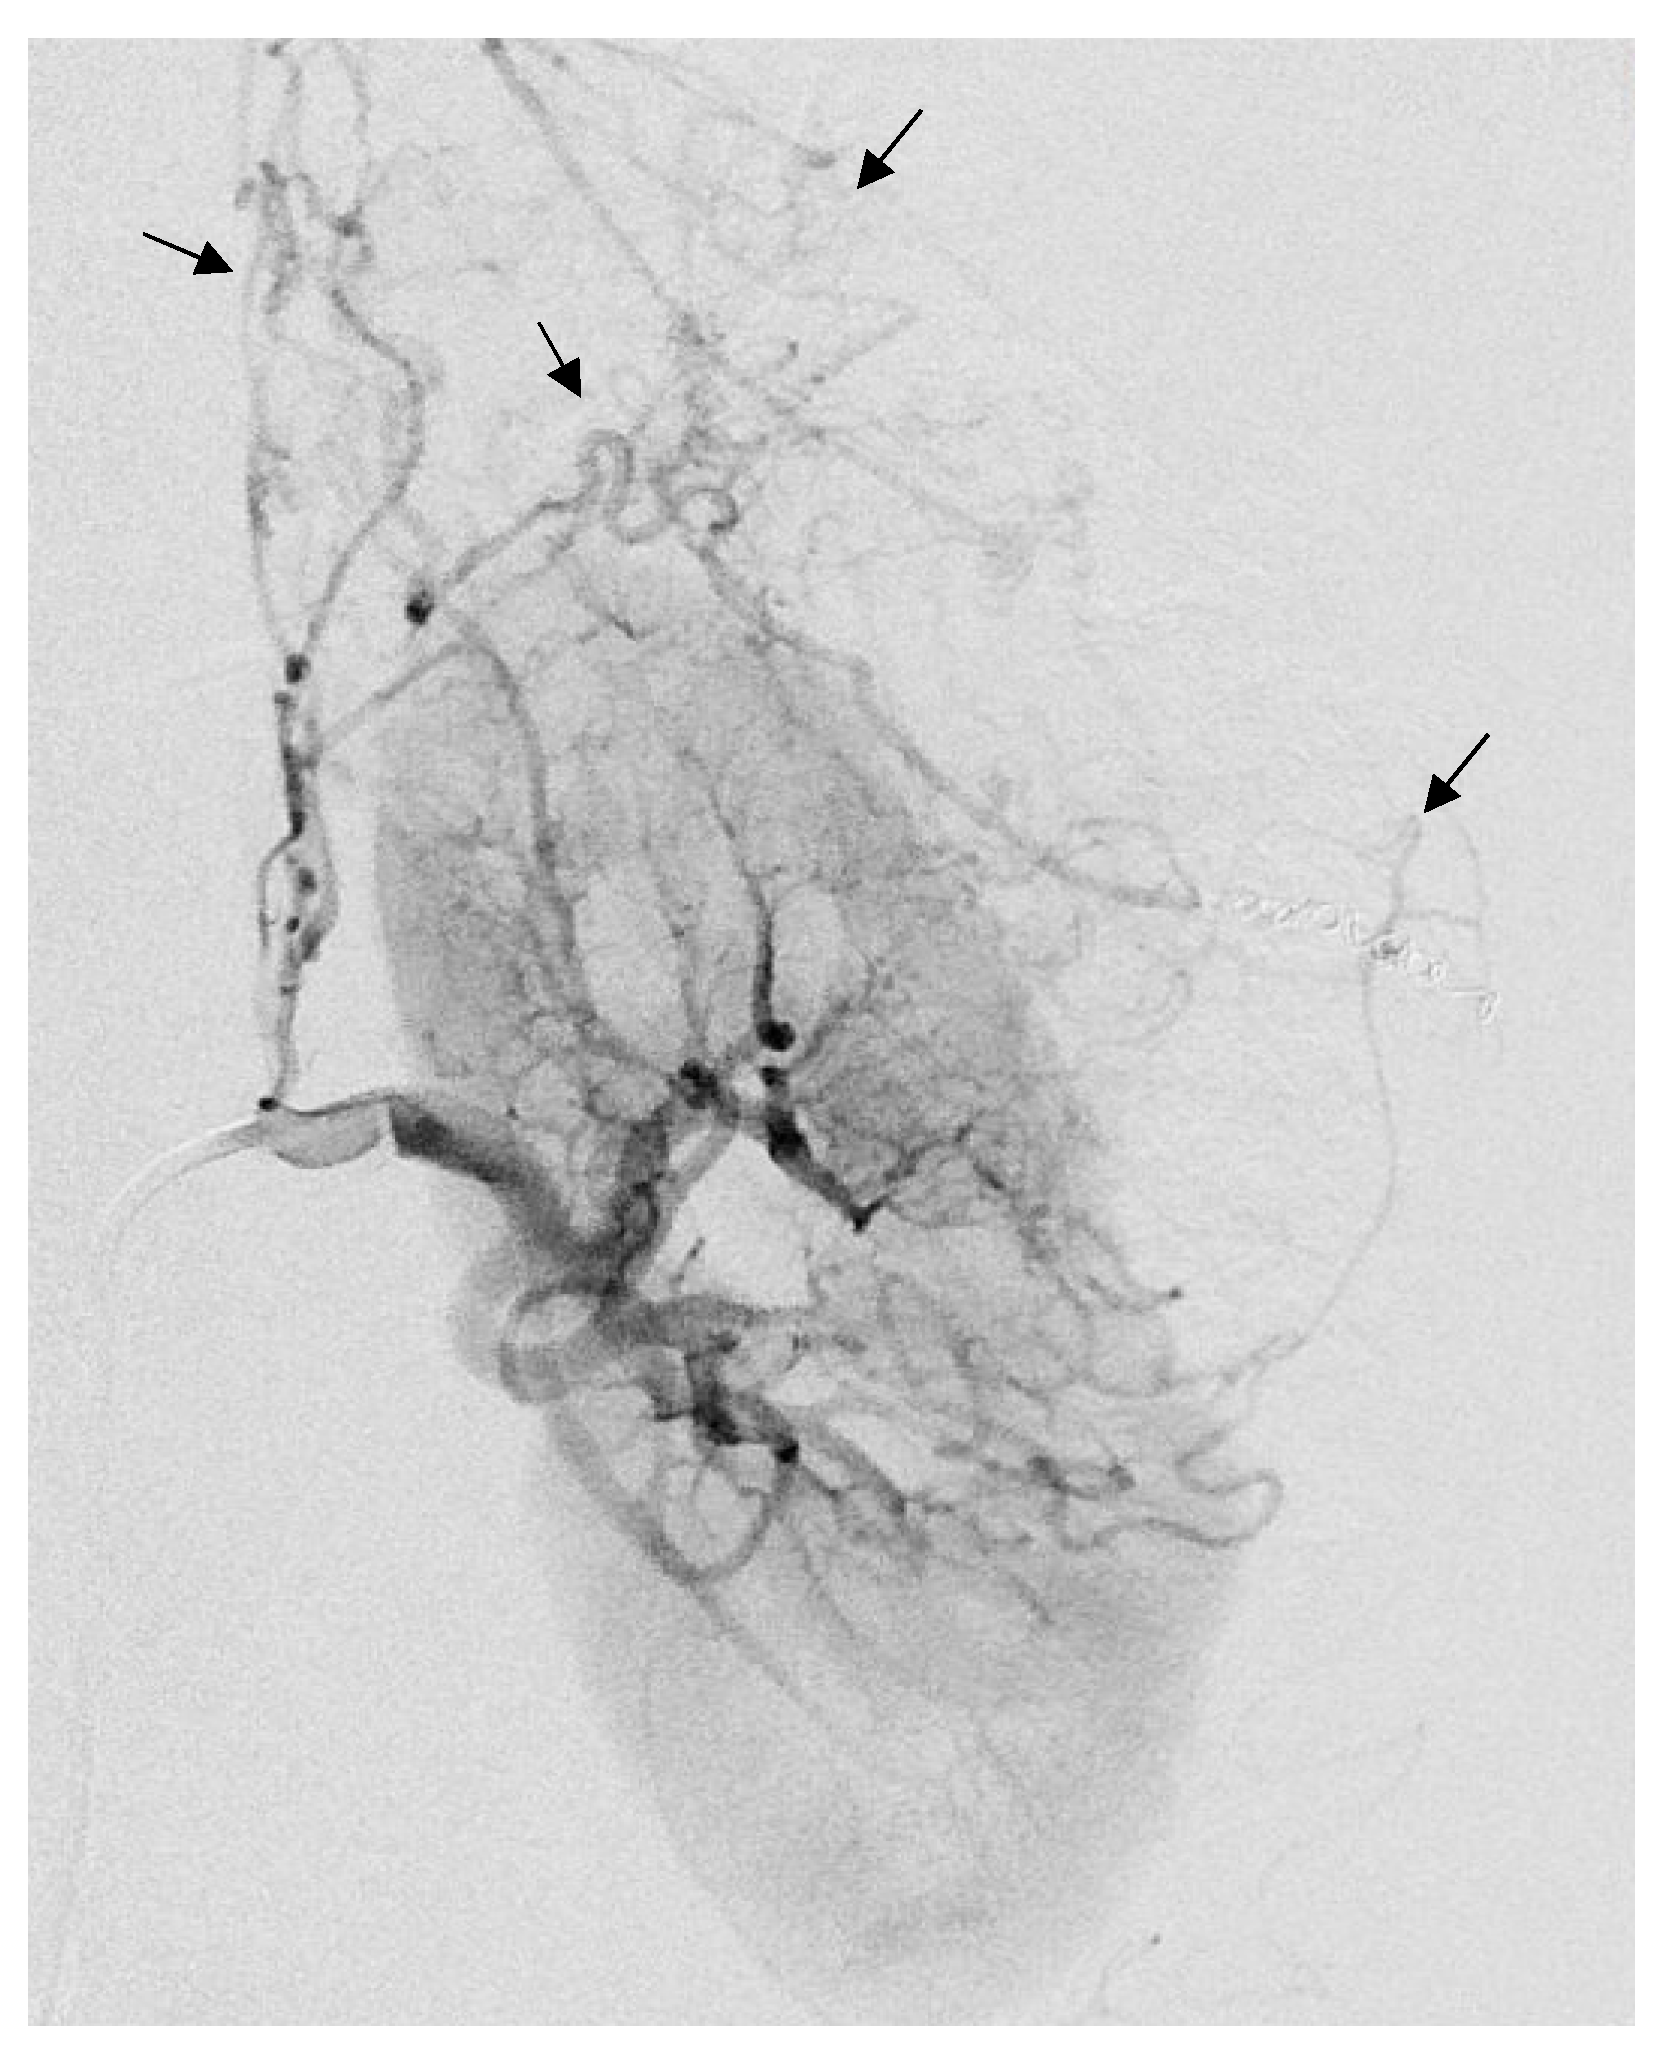

Figure 5.

Arteriogram showing a large left AML with anarchic vascularization (black arrows), as part of a Tuberous sclerosis complex in a 32-year-old patient.